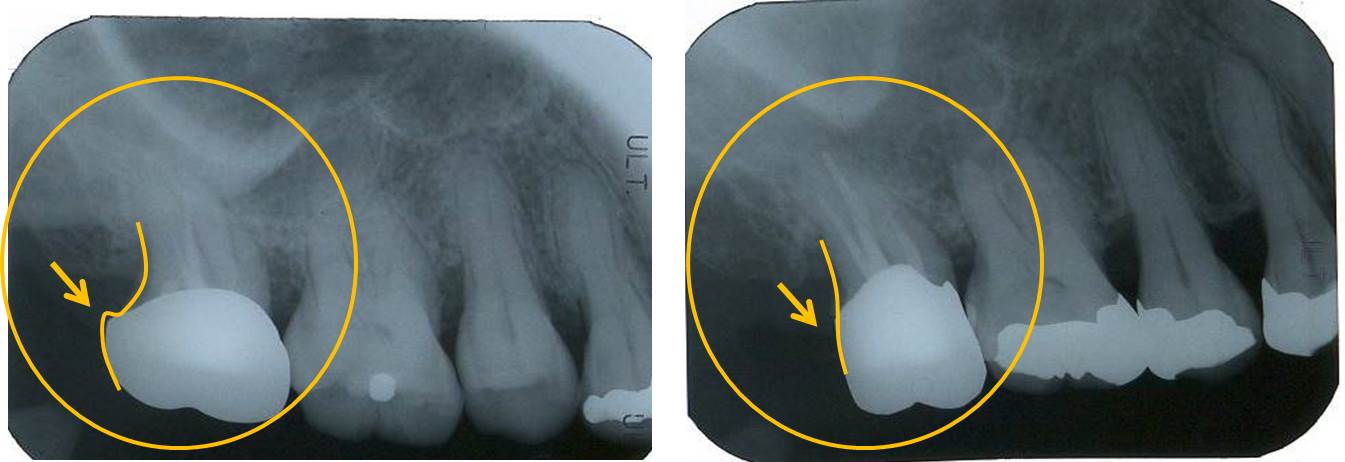

下写真は術前および術後の冠を丸で囲んでいます。あまり違いはないように見えます。

では、レントゲンで比較します。

左(術前)と右(術後)では冠の豊隆に差があるのがわかります。当然、右(術後)の方が歯ブラシが行いやすい冠の形態といえます。特に、奥歯は歯ブラシが届きにくいため良好なプラークコントロールが行いにくいため、歯周ポケットが改善しにくい部位でもあります。